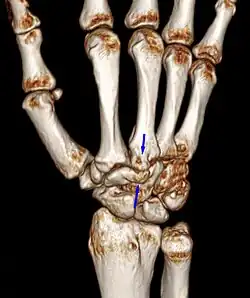

Carpal boss VR-3D-Reconstruction

Carpometacarpal bossing (or metacarpal/carpal bossing) is a small, immovable mass of bone on the back of the wrist. The mass occurs in one of the joints between the carpus and metacarpus of the hand, called the carpometacarpal joints, where a small immovable protuberance[1] occurs when this joint becomes swollen or bossed.

Carpometacarpal boss is uncommon and there is not much scientific data. Its etiology has yet to be fully defined, but can be congenital in the form of an accessory ossicle (os styloideum) or may be acquired from trauma, repetitive use, or degenerative osteophytosis.[3] The condition usually begins to show in the 3rd or 4th decade.